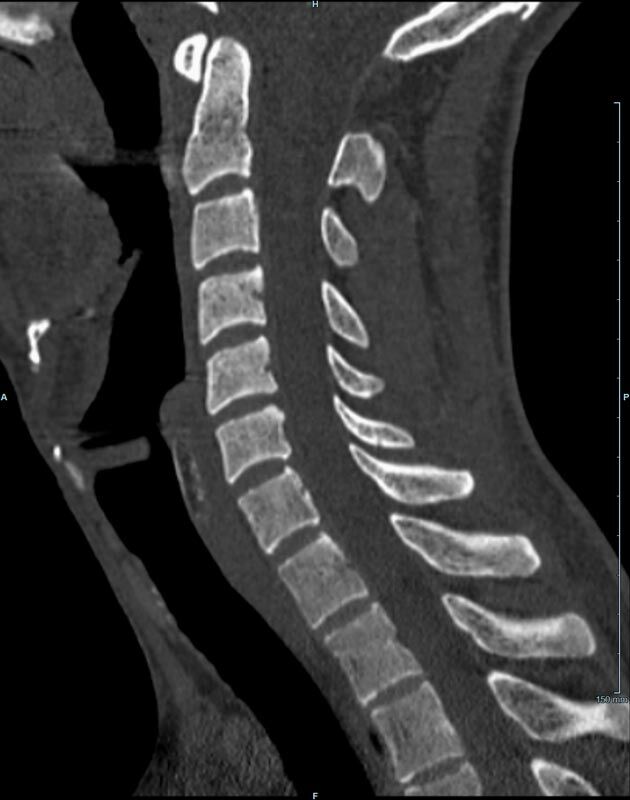

Wirbelsäule

• Darstellung von Frakturen, Tumoren und Bandscheibenveränderungen

Der Multislice-Scanner ermöglicht eine dem aktuellen Stand der Technik entsprechende, leitliniengerechte diagnostische Untersuchung sämtlicher Körperregionen. Darüber hinaus gestattet der neue Computertomograph auch eine für Arzt und Patient bequeme Durchführung CT-gestützter Interventionen wie z.B. Schmerztherapien der Wirbelsäule.